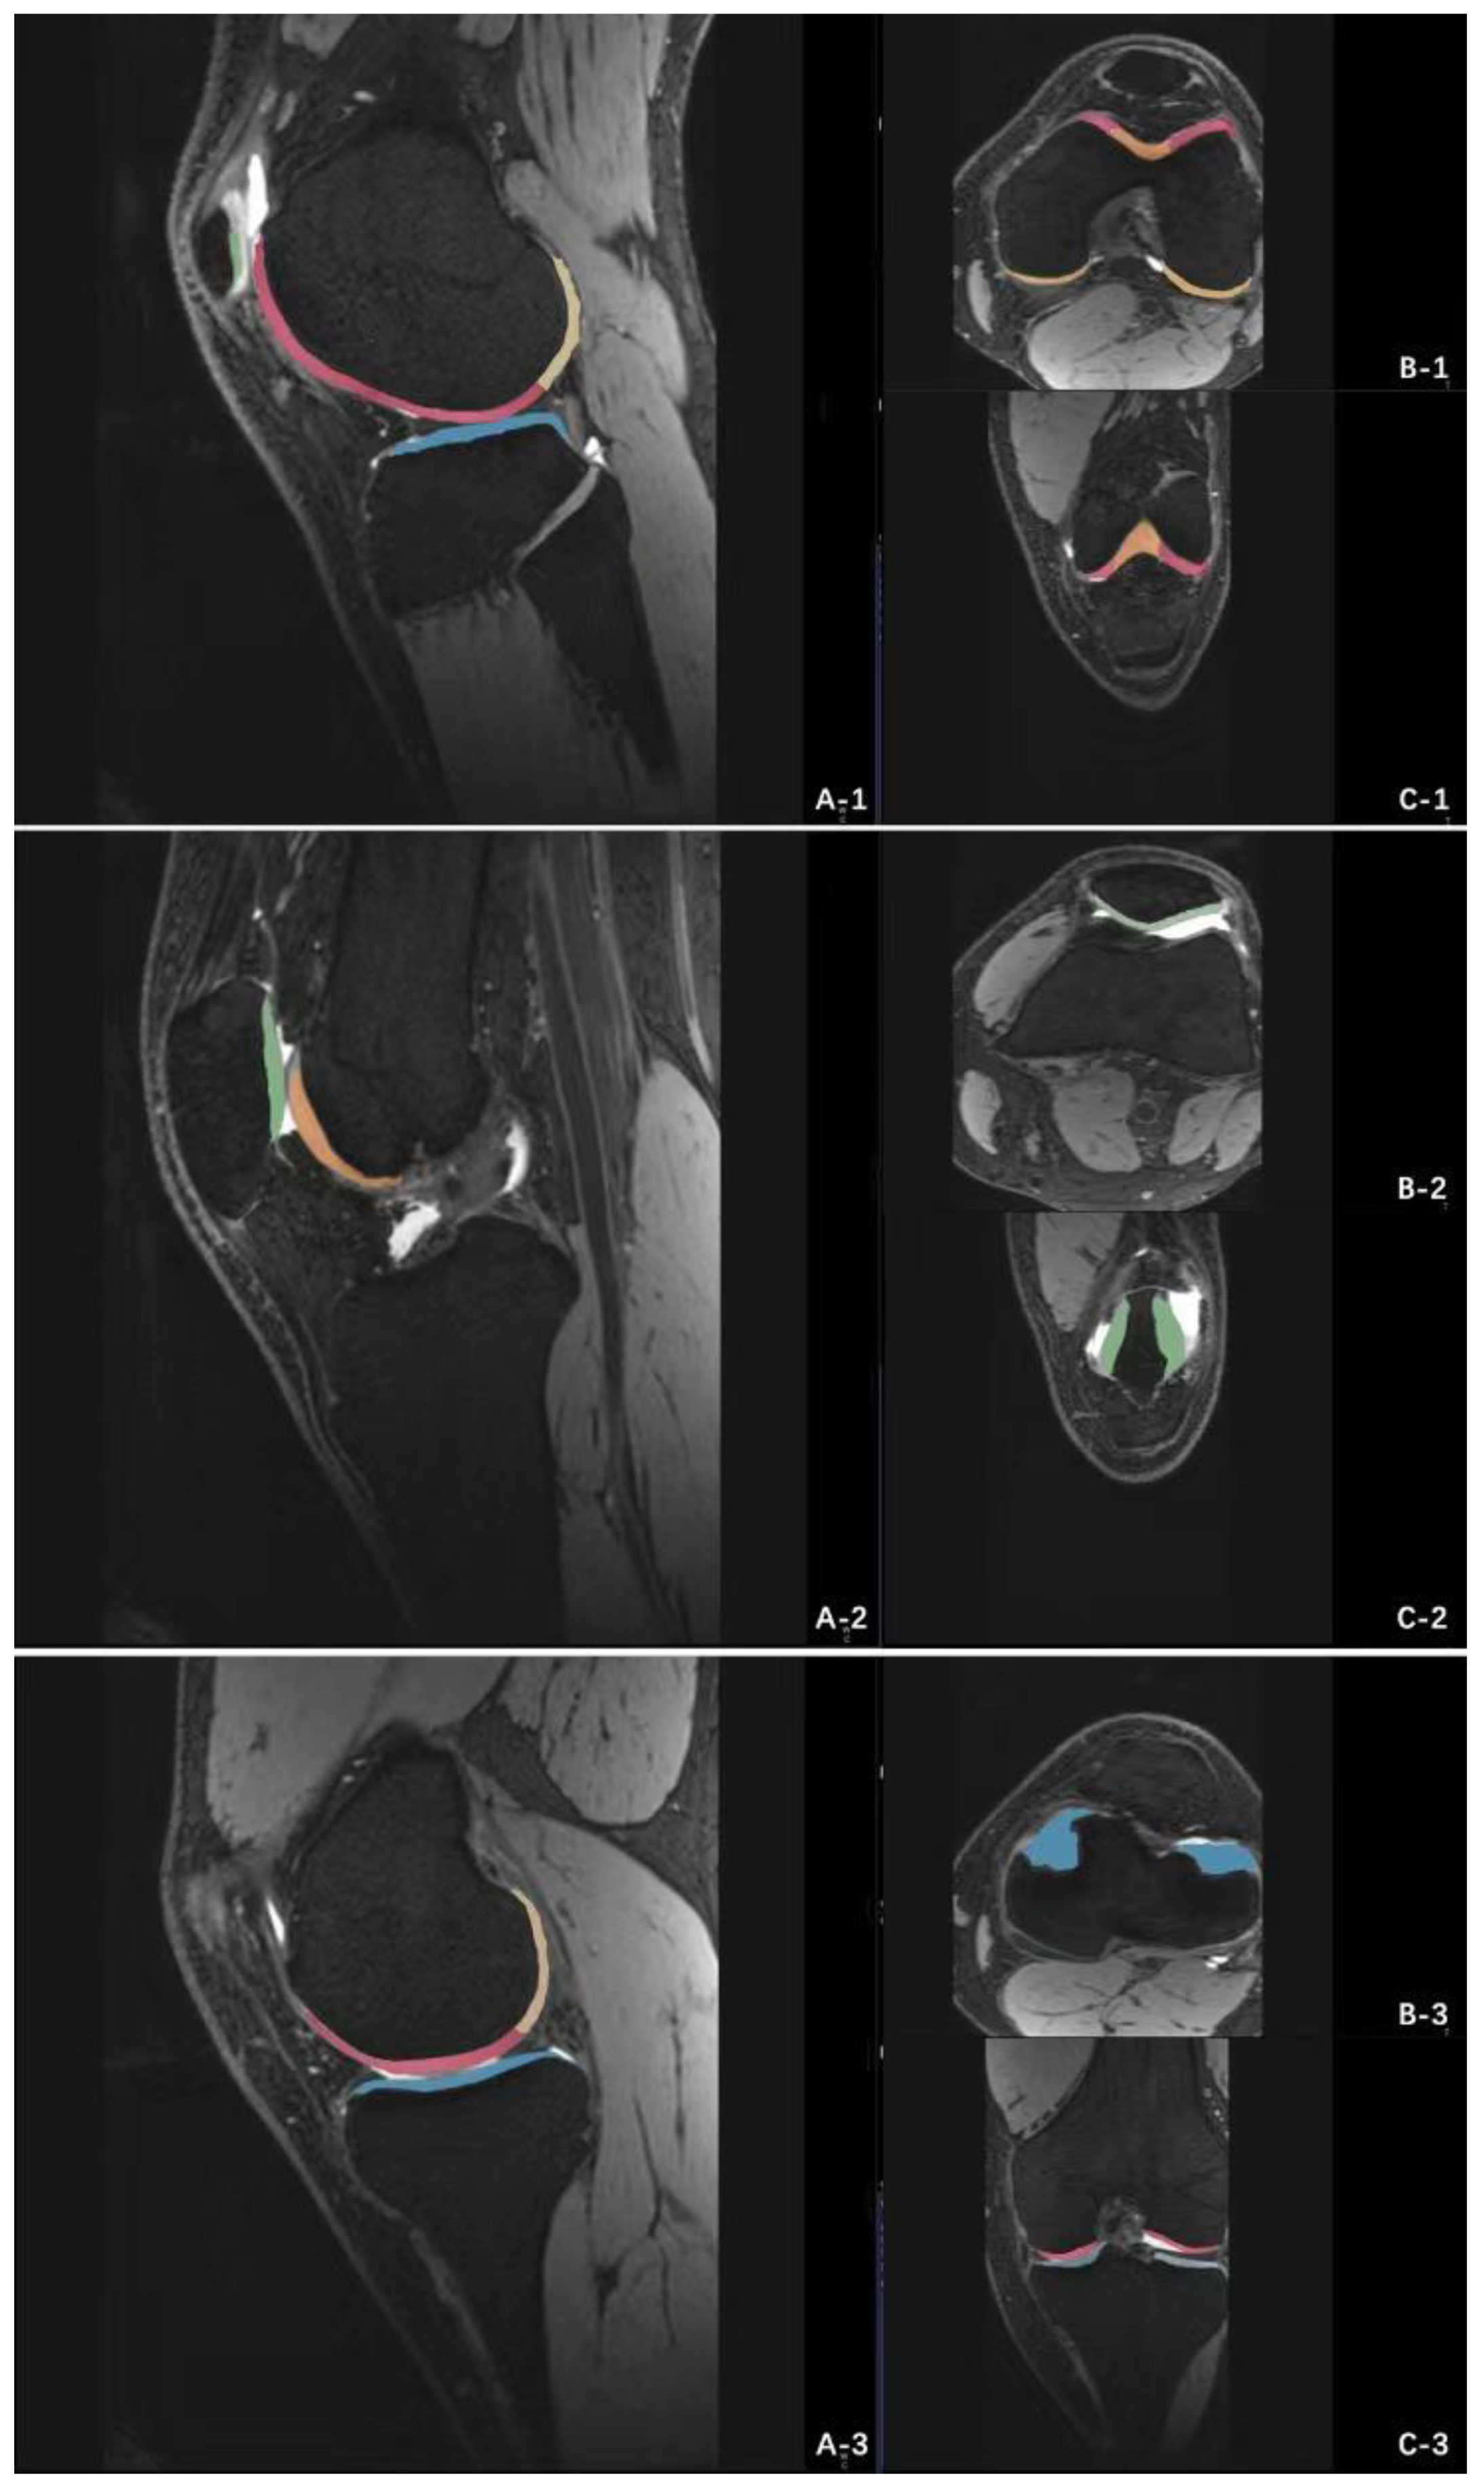

The T2 values of cartilage were measured on three consecutive sagittal planes of the medial, lateral tibiofemoral and patellofemoral joints respectively (Figure 4). When manually sketching the cartilage contour for measurement, tried to avoid the subchondral bone plate and joint fluid and remove the extreme value. The average T2 value of all 3 consecutive layers was the T2 value corresponding to the measured cartilage subregion. All data of T2 mapping sequence were imported into Siemens workstation (syngi mrb17 software) for reconstruction to obtain T2 mapping.

Figure 4.

Measurements of T2 value of cartilage in each sub region of knee joint. (A) the lateral tibiofemoral joint of the knee: the measurement sub zone 1 is the aLFC, the measurement sub zone 2 is the pLFC, and the measurement sub zone 3 is the LT; (B) patellofemoral joint of knee joint: the measurement sub zone 1 is P, and the measurement sub zone 2 is TrF; (C) medial tibiofemoral joint of knee joint: the measurement subzone 1 is aMFC, the measurement subzone 2 is pMFC, and the measurement subzone 3 is MT.